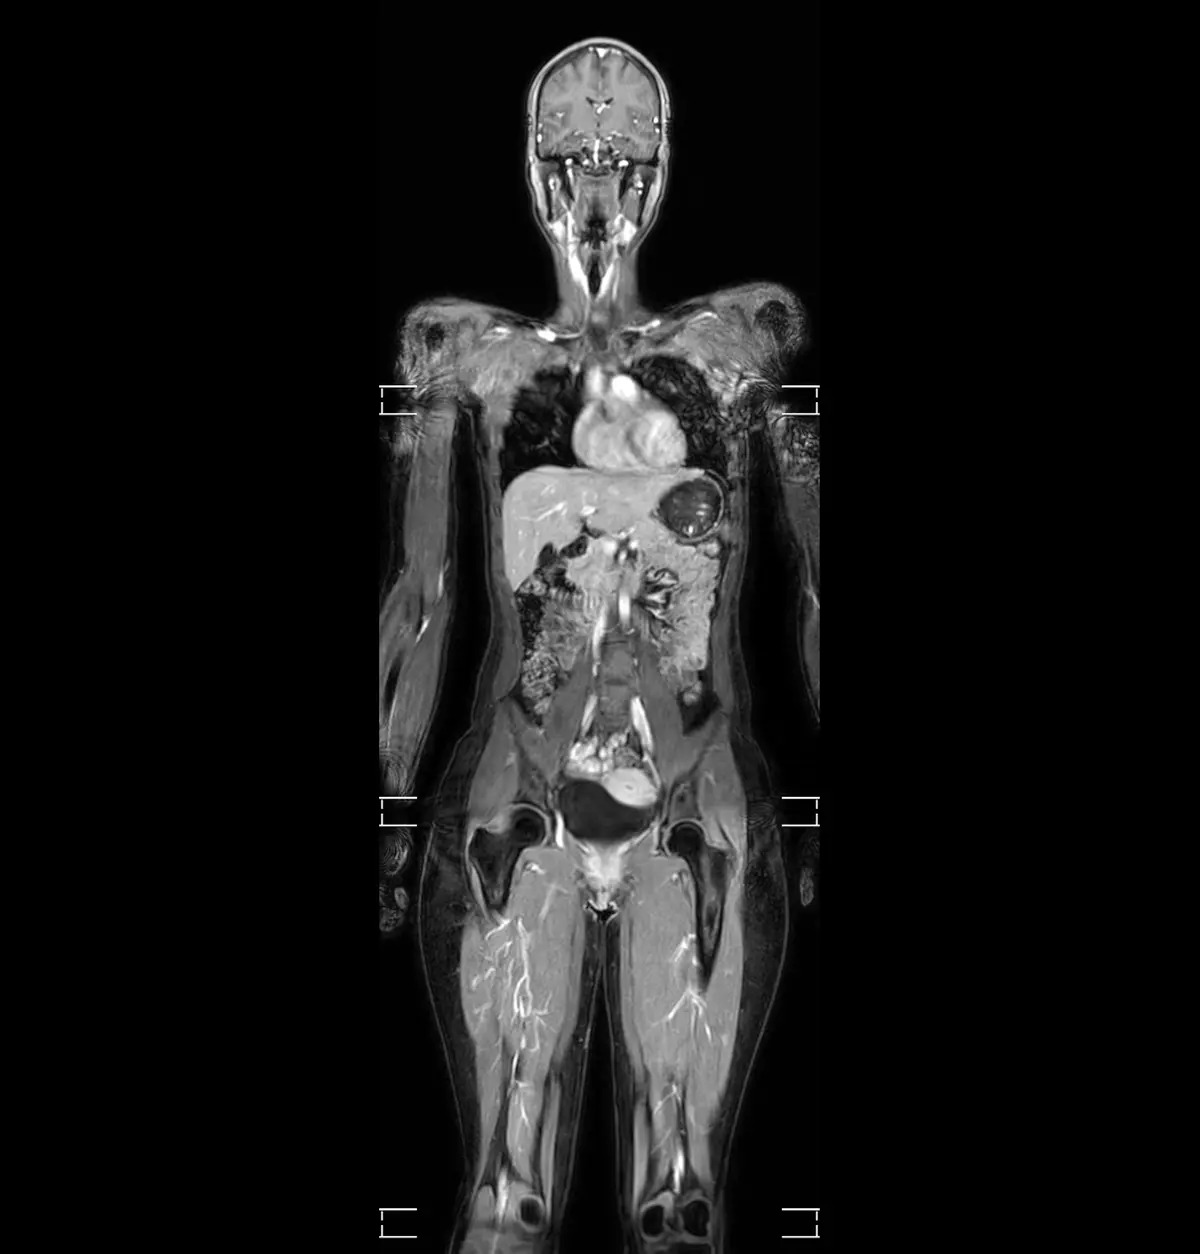

Ganzkörper-MRT – moderne Bildgebung zur Orientierung

Die Ganzkörper-MRT kann helfen, krankhafte Veränderungen im Körper frühzeitig sichtbar zu machen – z. B. bei familiären Risiken, Vorerkrankungen oder unklaren Beschwerden. Das Verfahren arbeitet ohne Röntgenstrahlung und liefert detailreiche Schnittbilder, z. B. zur Einschätzung möglicher Tumoren, rheumatischer oder degenerativer Prozesse.

Die Untersuchung dauert ca. 30–60 Minuten und erfolgt im Liegen. Auf Wunsch können Musik oder Filme zur Ablenkung beitragen. Die Kosten für Selbstzahler betragen ca. 860 € (ohne Kontrastmittel). Privatversicherte sollten die Erstattungsfähigkeit vorab klären.